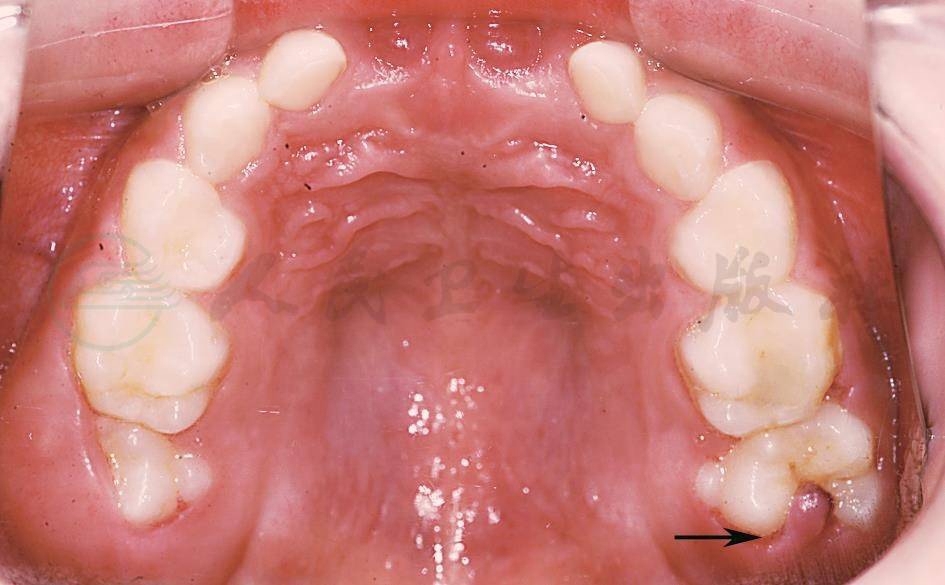

正在萌出的牙齿冠周牙龈组织充血,但无明显的自觉症状,随着牙齿的萌出而渐渐自愈。第一恒磨牙萌出时常见冠周红肿(图2),远中龈袋内可有溢脓,患儿诉疼痛,严重时炎症扩散可引起间隙感染、面肿。

图2萌出性龈炎

患儿,男,6岁,定期复查时发现16牙近中舌尖出龈,26牙远中龈瓣呈现水肿外观,覆盖于牙𬌗面的远中